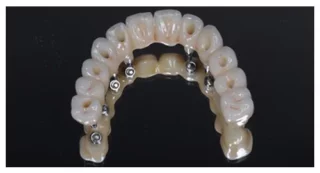

A fogimplantátum célja, hogy helyettesítse egy vagy több kihúzott fog funkcióját. Úgy kell elképzelni, hogy a beültetett fogimplantátum úgy működik, mint egy foggyökér, tehát a gyógyulását követően ellátható különböző fogpótlásokkal. Teljes fogatlanság esetén több fogimplantátumot szükséges beültetni, ezek száma 4-6-8, esetleg 10 db állcsontonként. Ezekre a fogimplantátumkra készül el és rögzül a fogpótlás, lehetőség szerint csavarozható megoldással. Az implantációs fogpótlások rendkívüli precizitással kell készüljenek, erre a digitális (CAD-CAM) gyártás technológia a legalkalmasabb.

A fogimplantátumra készített pótlások anyaga lehet fémtartalmú is, de rendelőnk a biokompatibilitás és pontosság miatt szinte kizárólag cirkónium alapú megoldásokkal áll a páciensek rendelkezésére. A koronák, hidak átmenő csavarral rögzülnek a fogimplantátum belsejében kialakított “fészekbe”, így szükség esetén károsítás nélkül eltávolíthatóak, tisztíthatóak, javíthatóak.

Az eljárás lényege, hogy egy forradalmi újításként az állcsontok elülső, úgynevezett tömör csontos régiójába kerül beültetésre alul minimum 4, illetve felül minimálisan 6 darab fogimplantátum oly módon, hogy a hátsók egy bizonyos ferde szögben rögzülnek. Az esetek túlnyomó többségében még idős korban is található alkalmas terület a front régióban e beavatkozás elvégzésére. A fogimplantátumokhoz legtöbbször csavarozható módon tudjuk rögzíteni az új, teljesen fix fogsorokat, így akár egy napon belül a korábbi kivehető protézisek helyére esztétikus, funkcióstabil rögzített fogsor kerül. A fogsor rögzítésére szolgáló fogimplantátum beültetése esetén a gyógyulási idő 3-6 hónap, melynek leteltével van lehetőség a végleges, akár a legmagasabb esztétikájú cirkónium körhidak elkészítésére, a teljes fogsor rögzítésére.